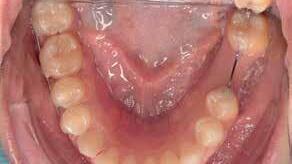

A 33 year old male presented to the orthodontic clinic referred by his prosthodontist . His main concern was the overeruption of maxillary right and left second molar due to bilateral loss of second and third mandibular molars that rendered the placement of prosthodontic implant and crown not possible. The patient had a 4 unit bridge, to replace missing maxillary right first and second premolar, with a root canal treatment and crown done on maxillary right lateral incisor and left second premolar. The patient’s main condition was to reduce the orthodontic system to a minimum with no visible appliances due to the nature of his work in sales.

Placement of temporary anchorage devices (Miniscrew) in the buccal and palatal side of the maxillary second molars in order to orthodontically intrude those teeth and create the required biological space for implant and crown placement in the mandibular posterior molar region(Figure 3).

Interproximal reduction in the area between maxillary first and second molar is necessary to allow the intrusion of the second molar without being hindered by the proximal contact of the first molar.(figure 4)

- 2 Buccal (1.6 mm diameter 8mm length) infra-zygomatic mini screw on upper 2nd molars of each side were placed this high in order not to interfere with the intrusive movement.

- 2 Palatal (1.8 mm diameter 8 mm length) placed in the midpalatal suture and another halfway the distance between the left second molar and the mid-palatal suture .

- The mini-screws were placed in a way that the resultant forces on each side are 120-150 g of force leading to close to pure intrusion of 2nd molars .

The patient presented to the clinic every 6 weeks for chain replacement because slow intrusion is needed. The 2nd molar was blocked below the distal contact area of the 1st molar, monitored IPR was carried out between the 1st and 2nd molar on both sides to facilitate the intrusive movement. The treatment took 10 months with 7 appointments.

- After 7 months of active intrusion, the level of the 2nd molars was found appropriate, but the intrusion force was maintained as a means of retention for 2 more months.

- During that time, the patient placed 2 implants in the lower posterior edentulous areas (1 on each side)

- Debonding was done, and a thermoformed plastic retainer was manufactured and worn by the patient at all times except at meals to act as retention until the final crowns are placed on the implants which will then prevent relapse of the upper 2nd molars .